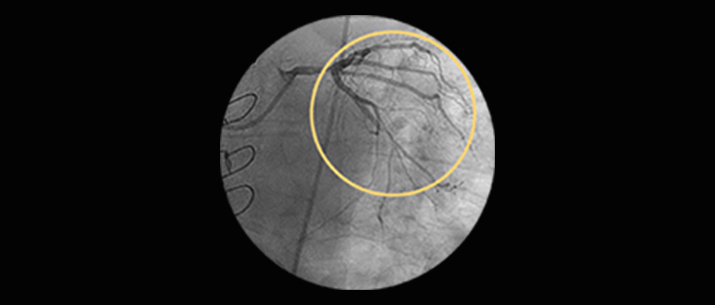

Significant left main CAD (greater than 50%) is found in 3-4% of all patients who undergo coronary angiography.1